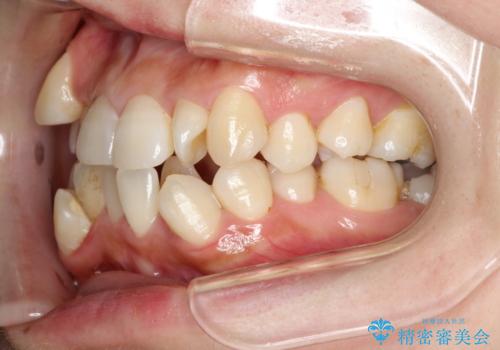

- 前歯の見た目の改善を希望され来院された患者様です。

初診時の歯並びの状態としては、上下に強いガタガタがある状態であり、それが原因で口腔内の清掃状態も極めて悪い状況でした。

スペースの不足量が著しく、上下左右の抜歯を伴うワイヤー矯正にて治療を行いました。